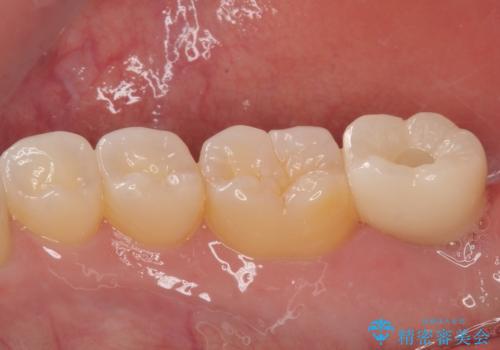

抜歯された骨の穴は、インプラント埋入時にはまだ大きな窩洞となっていましたが、径の大きいワイドインプラントを選択することで、埋入時に十分な安定を獲得することができました。

後方には欠損が残っていたため、補填材を填入しました。

術後にインプラントが骨から脱落することがありますが、特筆するトラブルなどなく、最短の3ヶ月で治療を終えることができました。